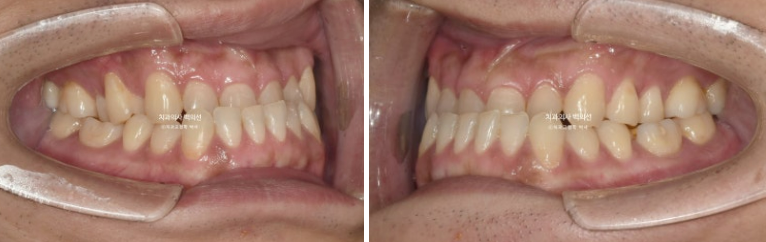

중심선은 잘 맞으며

23.07~25.04

어금니 교합은 좋습니다.